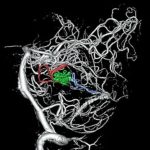

脳血管撮影

手術前

手術後